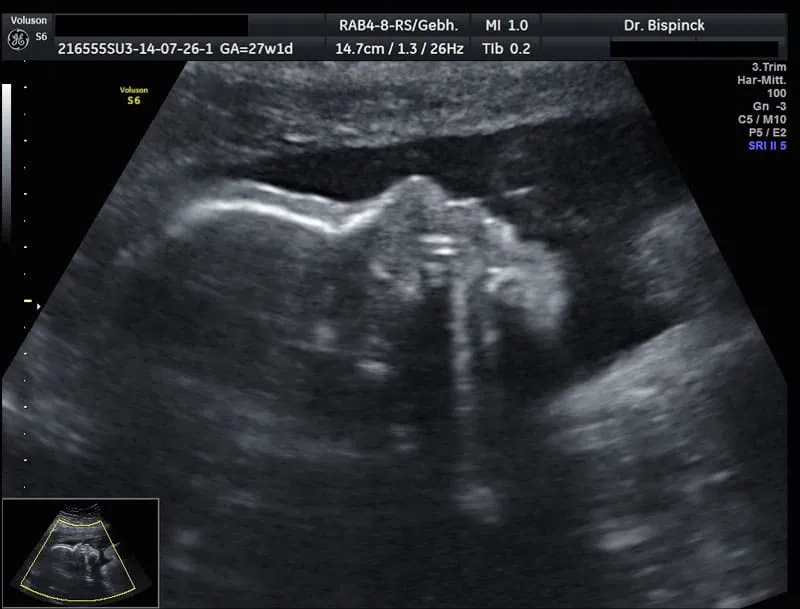

Ultraschall in der Schwangerschaft

Bei Bekanntwerden der Schwangerschaft wird die erste Ultraschalluntersuchung in der Regel von der Scheide aus durchgeführt. In der 7. SSW gelingt meistens die Darstellung eines kleinen Embryos mit Herzaktion. Abgesehen von dieser Untersuchung sehen die Mutterschaftsrichtlinien aktuell drei Ultraschalluntersuchungen vor:

Bei der zweiten Untersuchung (19.- 22. SSW) erfolgt der sog. erweiterte Basisultraschall zur Beurteilung der Lage und des Wachstums des Kindes und der kindlichen Organe. Hier werden sämtliche einsehbare Organe (z.B. Herz, Wirbelsäule, Gehirn, Nieren und Harnblase) hinsichtlich ihrer korrekten Anlage und Entwicklung untersucht. Außerdem wird die Lage des Mutterkuchens festgestellt und kann in der Regel das kindliche Geschlecht sicher dargestellt werden.

Ziel dieser Untersuchung ist es, soweit wie möglich kindliche Fehlbildungen auszuschließen, Risiken zu erkennen, um ggf. darauf reagieren zu können.

Die dritte Ultraschalluntersuchung erfolgt in der 29.-32. SSW. Sie dient der Kontrolle des kindlichen Wachstums, seiner Lage und der Fruchtwassermenge.